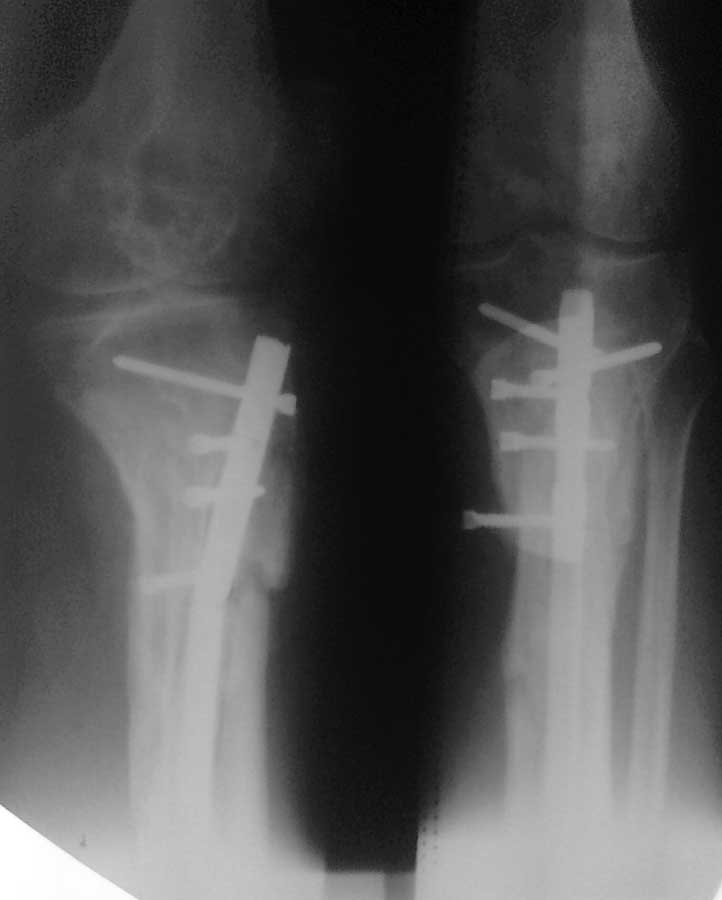

Все таки решились на штифт с антибиотическим покрытием. Выставляю R, в целом считаю неплохо вроде получилось.